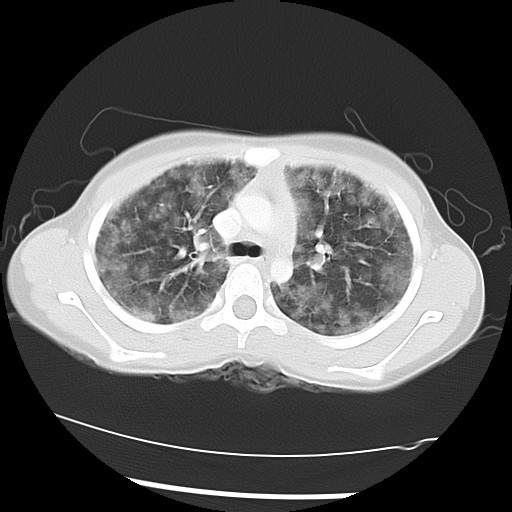

The following screen shows the images from the Chest CT:

| Figure 2-a | Figure 2-b | Figure 2-c |